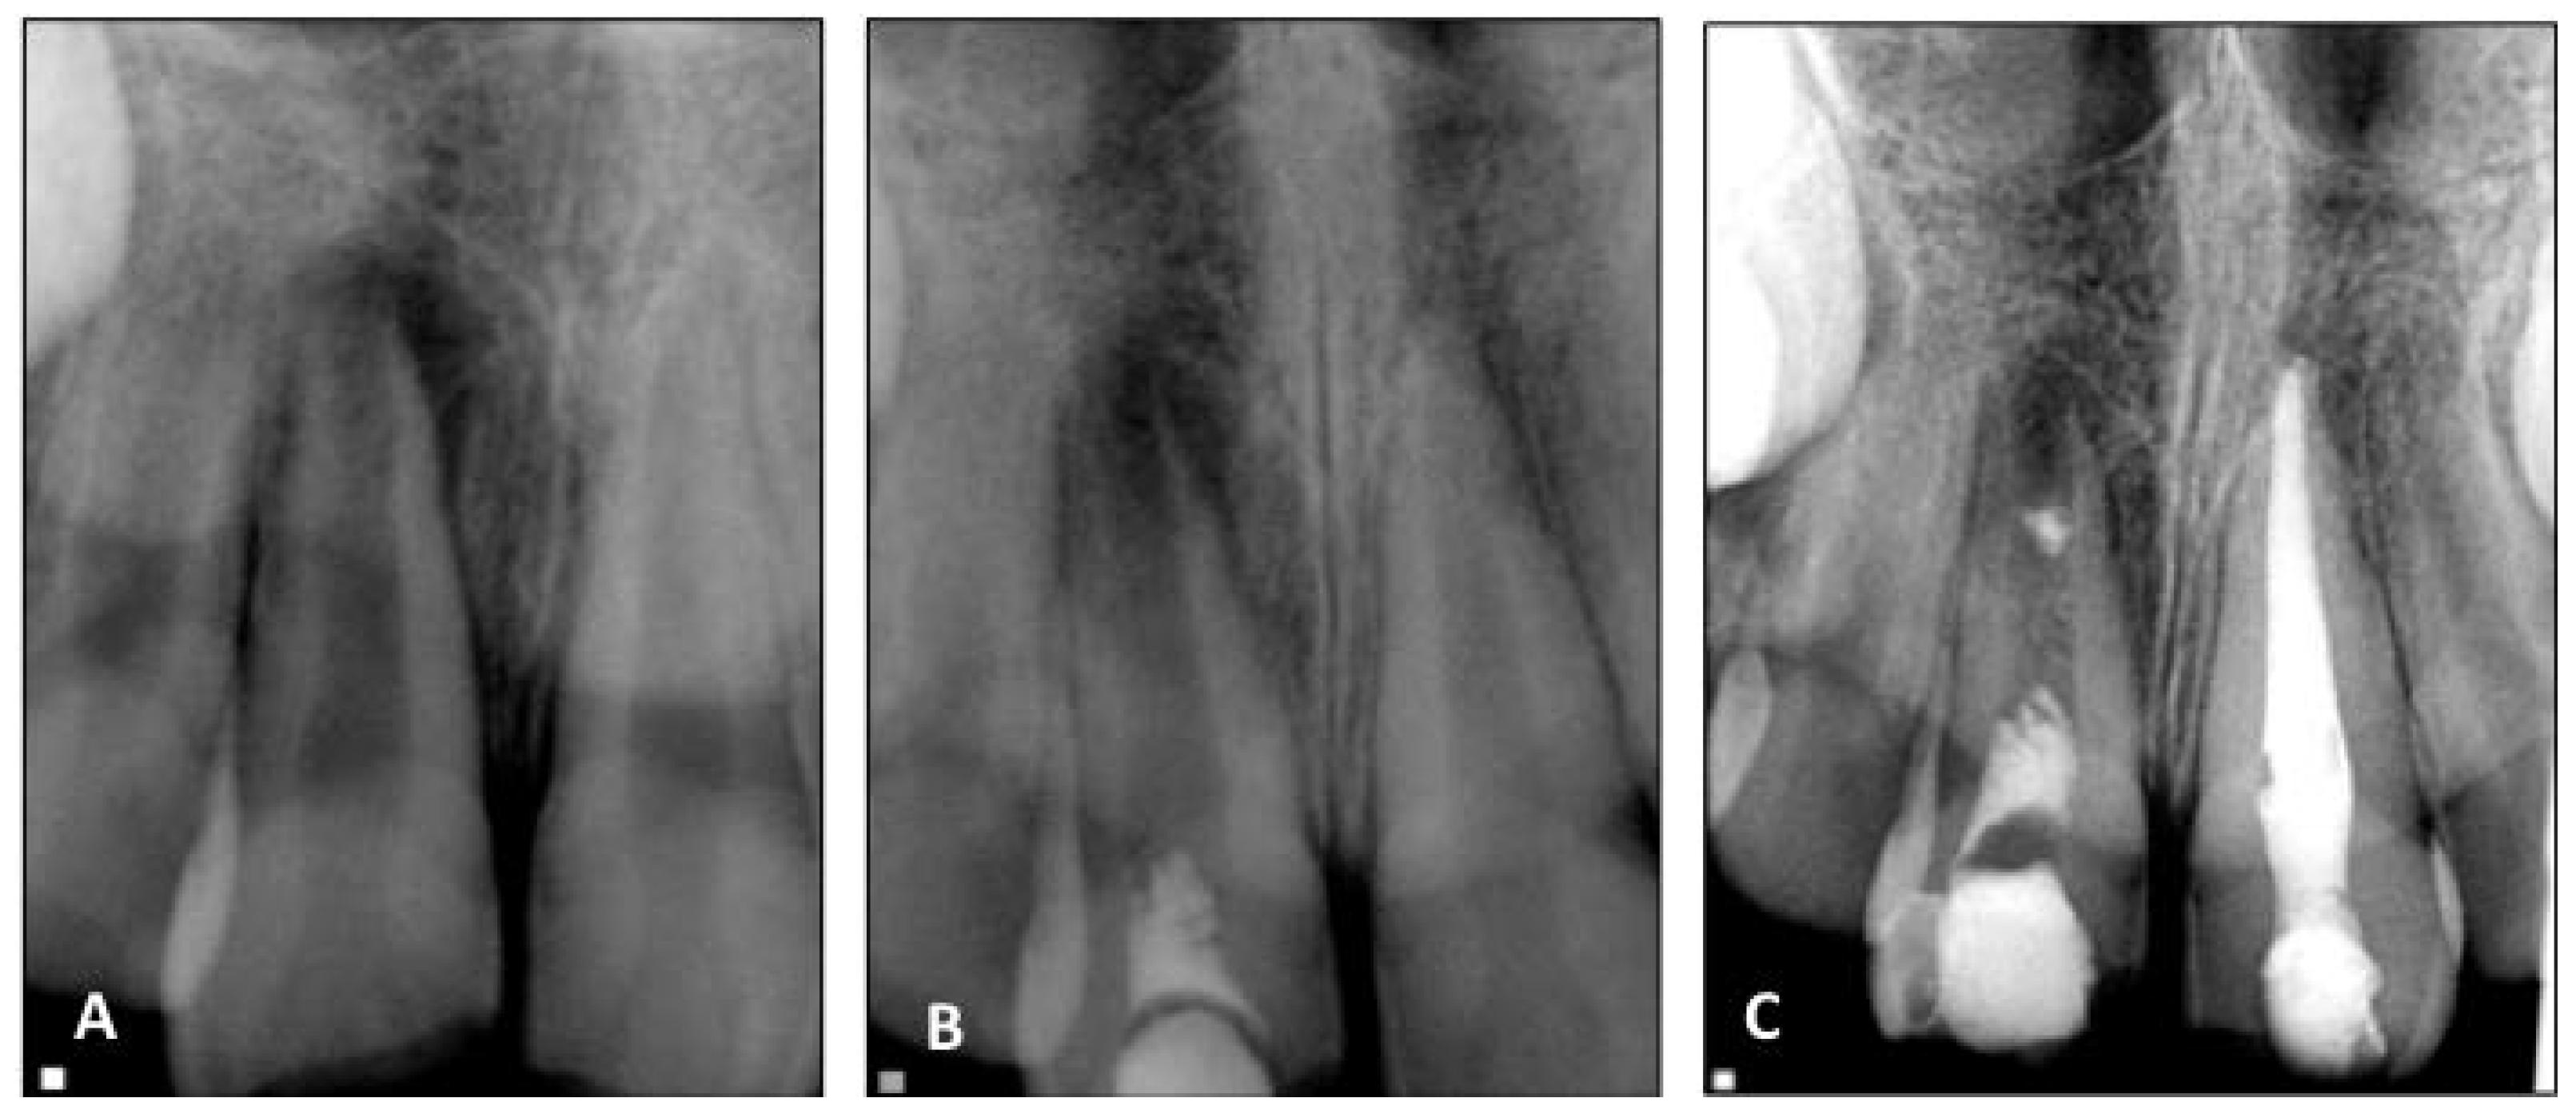

10. Treatment of Teeth with Persistent Apical Periodontitis after Root Canal Therapy

- Saoud, T.M.A.; Huang, G.T.-J.; Gibbs, J.L.; Sigurdsson, A.; Lin, L.M. Management of teeth with persistent apical periodontitis after root canal treatment using regenerative endodontic therapy. J. Endod. 2015, 41, 1743–1748. [Google Scholar] [CrossRef] [PubMed]